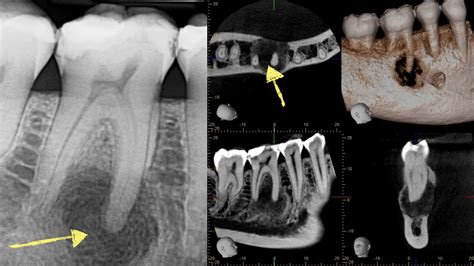

When you visit a dentist or an oral surgeon, they will perform a physical examination to check for tender areas, redness, and swelling. However, a clinical exam is rarely enough to confirm a diagnosis. Professionals typically rely on imaging and laboratory tests to confirm a jaw bone infection.

X-rays To identify bone changes or large abscesses.

CT Scan Provides detailed 3D views of the bone structure.